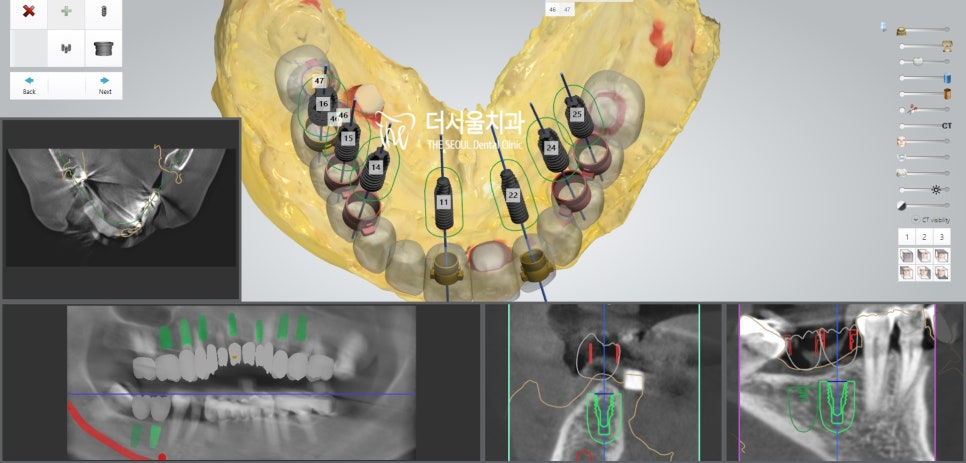

더서울에서 항상 했던 그대로

디지털 분석을 통해 인접치,

주변 조직과의 위치 관계를 파악했습니다.

모든 고려 사항을 종합적으로 판단을 했으면

계산된 위치에 맞춰 픽스쳐를 심어드렸습니다.

개수가 많기 때문에 걱정이 되었지만,

미리 제작된 가이드를 사용하여 수술을 진행하였더니

즉시식립 임플란트 과정을

정확하고 안전하게 끝마칠 수 있었습니다.